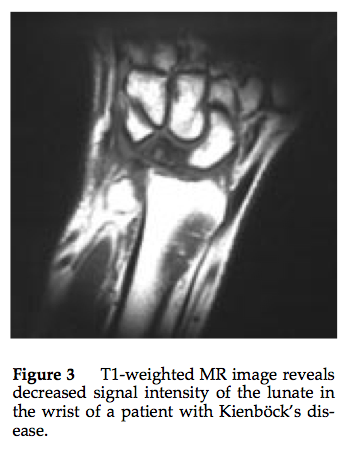

Diagnosis? Classification

Keinboch’s - Litchman Classification

Imaging to help define collapse of lunate